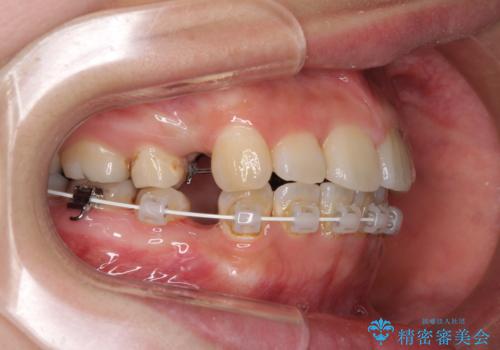

デコボコと膨らんだ口元 ハーフリンガルによる抜歯矯正とインプラント補綴治療

- ハーフリンガル

- 前歯のデコボコと上顎の前突感による口の閉じにくさを気にして来院された患者様です。

目立たない装置を希望されたので、上顎が裏側装置のハーフリンガルを選択し、上下左右の小臼歯(計4歯)を抜歯して矯正治療を行うこととしました。

また、左下の奥歯は抜歯が必要な歯であったため、矯正治療中の良いタイミングで抜歯とインプラント埋入を行い、矯正治療後にオールセラミッククラウンで補綴治療を行うこととしました。

デコボコの解消までは非常にスムーズでしたが、咬合力が強いためか、スペースを閉じるまでに長い期間を要しました。

矯正治療途中にインプラント埋入と仮歯の装着を行ったことで、しっかりとした奥歯の咬み合わせで終了させることができました。